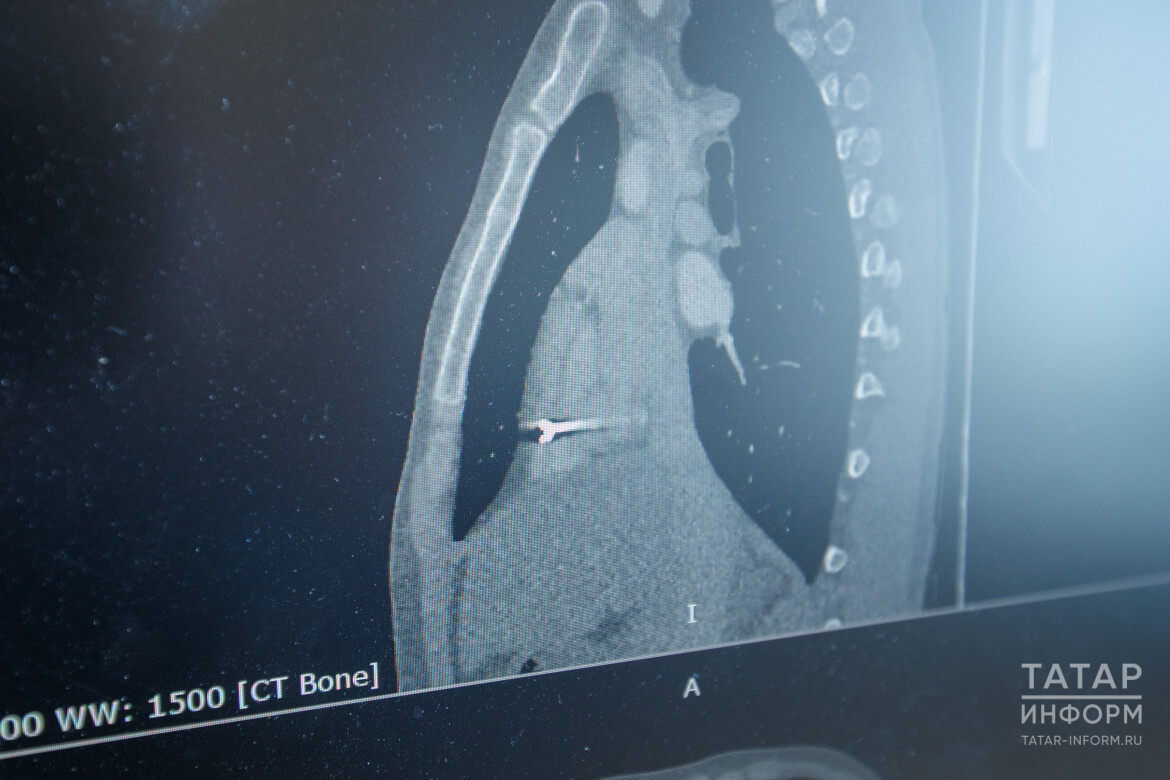

По снимкам рентгена и КТ понять, в какой именно области находится осколок, было невозможно. Тогда медики РКБ обратились к коллегам из МКДЦ. Кардиохирурги приехали в военный госпиталь, провели свои исследования.

По снимкам рентгена и КТ понять, в какой именно области находится осколок, было невозможно

«По исследованиям, мы приблизительно подтвердили локализацию осколка: либо это сердечная сумка – перикард, либо это стенка правого желудочка, либо это правая плевральная полость – где находится правое легкое», – объяснил заведующий первой кардиохирургией МКДЦ Артур Закирьянов.